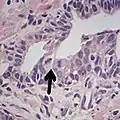

Intraductal carcinoma of the prostate with very patchy basal cells identified by immunohistochemistry. At least some of the glands lacking basal cell immunoreactivity represent intraductal rather than invasive carcinoma (a haematoxylin and eosin, b CK 5/6)[19]